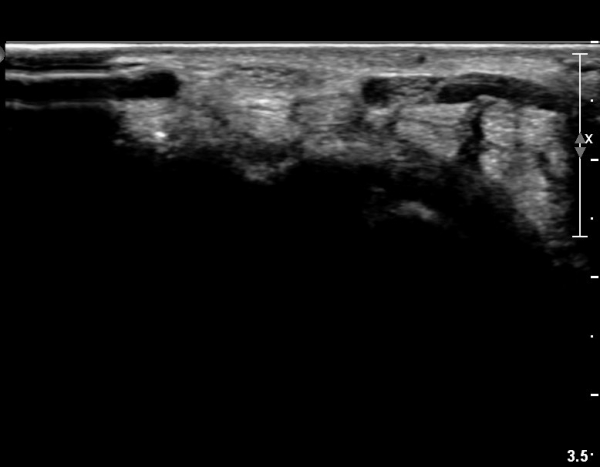

Å½ÃËÀÚ¸¦ ¸»´ÜÀ¸·Î À̵¿ÇÏÀÚ  Á¤Áß½Å굥 ¿äÃø ÀϺΰ¡ Àú¿¡ÄÚ Á¾±«·Î °üÂûµÊ(»çÁø 2).

ÀÌ·± ¸ð½ÀÀº ¼Õ¸ñÀÇ ¿ù»ó°ñ ºÎÀ§(»çÁø 3, 4)¸¦ Áö³ª ¼ö±Ù°ü ±ÙÀ§ºÎ ±îÁö À̾îÁü(»çÁø 5).

ÇÏŰ½ºÆ½(°íÁÖÆÄ) ŽÃËÀÚ¸¦·Î °üÂûµÈ ¸ð½À¿¡¼­ Á¤Áß½Å°æ ºÎºÐ ½Å°æ´Ù¹ßÀÇ Àú¿¡ÄÚ

º¯È­°¡ ¶Ñ·ÈÇÔ(»çÁø 6, 7).